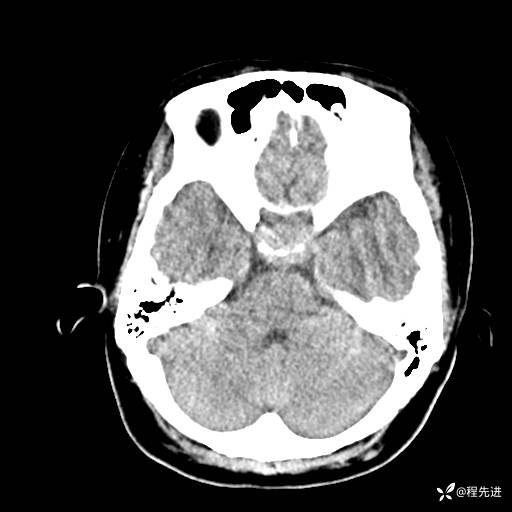

CT平扫: